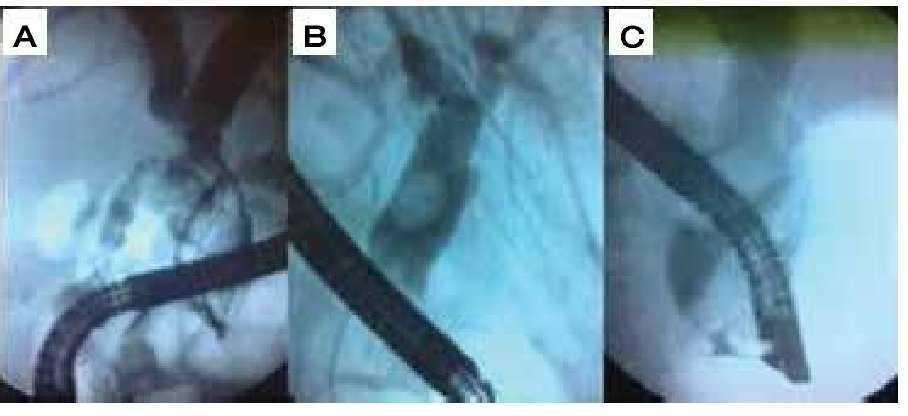

En cuanto al tamaño de los litos en su diámetro mayor, el promedio fue 19.2 mm (16 mm a 25 mm). El diámetro mayor del colédoco promedio fue de 23.5 mm (15 mm a 34 mm) (Figura 1).

Figura 1. Colangiografías de algunos pacientes del protocolo. A) Paciente 6. B) Paciente 7. C) Paciente 8.